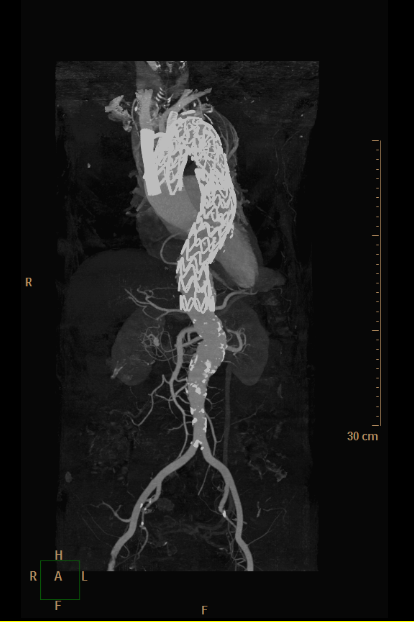

▲ 实例:覆膜支架腔内治疗+左侧锁骨下动脉单开窗(血管外科王兵教授团队)

▲ 实例:覆膜支架腔内治疗+左侧锁骨下动脉、左侧颈总动脉双开窗(血管外科王兵教授团队)

▲ 实例:主动脉瘤合并夹层腔内治疗+弓上三分支腔内重建(血管外科王兵教授团队)